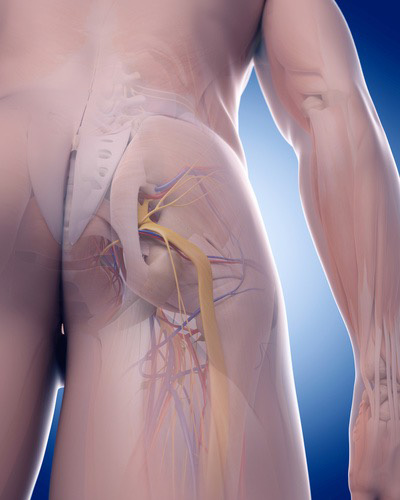

このセッションでは、血管・靭帯・神経をあなたの臨床に取り入れやすくするために筋膜との関係性を明らかにします。例えば腕神経叢は斜角筋と繋がりがありますし、坐骨神経は梨状筋との繋がりがあります。この知識さえあれば、どのタイミングで血管や神経を見ればいいのかがわかり。明日からの臨床ですぐに結果を出すことができるでしょう。

坐骨神経痛は殿部~下肢後面に走る痛みとシビレを症状です。ヘルニアや腰部脊柱管狭窄症の疾患でよる表れる症状です。ヘルニアや腰部脊柱管狭窄症の疾患がなくても、例えば梨状筋がこの坐骨神経に刺激を与え神経症状が生じているケースもあります。刺激とは圧迫や滑走性低下による摩擦などを表していますが、坐骨神経とその周囲組織のリリースをすることで今まで取りきれなかった神経痛を解消させることができます。

この坐骨神経痛リリーステクニックを学ぶことであなたは、、、